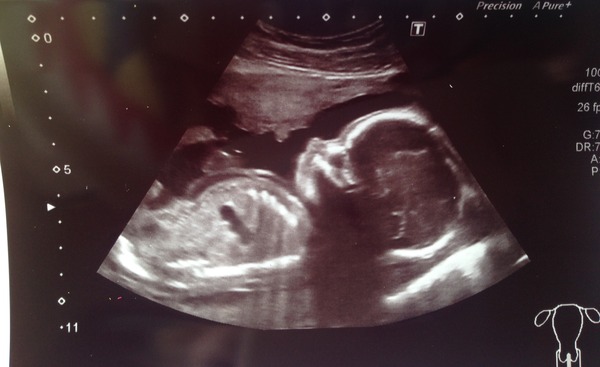

brickiemum2 · 22/08/2015 11:33

Had my anomaly scan yesterday and everything was perfect Grin baby still very active and kept its hands up by its face most of the time. Still firmly in team yellow, we had to look away from the screen several times lol as she was doing her checks. My bump is getting there but I'm definitely carrying all over like I did with ds.

brickie Lovely scan pics, I'm glad baby is doing so well Smile